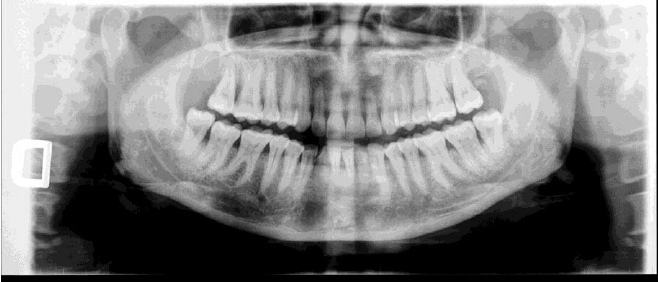

La continua innovazione e ricerca tecnologica in campo odontoiatrico hanno finalmente portato alla realizzazione di uno scanner digitale che rileva le impronte dentali. Lo scanner di dimensioni medio contenute effettua una scansione tridimensionale del dente o dei denti che devono essere trattati. L’analisi viene successivamente elaborata da un software che ricostituisce le fattezze del cavo orale in laboratorio.

L’impronta ottica offre il vantaggio di raggiungere obbiettivi terapeutici con tempistiche migliori e costi inferiori, ma sempre con qualità elevata. Grazie a questa nuova tecnologia è possibile ingrandire ampiamente le immagini e notare i dettagli nell’immediato anche per scopi operatori.

Uno dei maggiore benefici dell’impronta ottica si trova nella possibilità di modificare all’istante l’immagine senza dover far ritornare il paziente a studio. Uno degli ambiti che più beneficia della tecnica dell’impronta digitale ottica, è senza dubbio l’ortodonzia